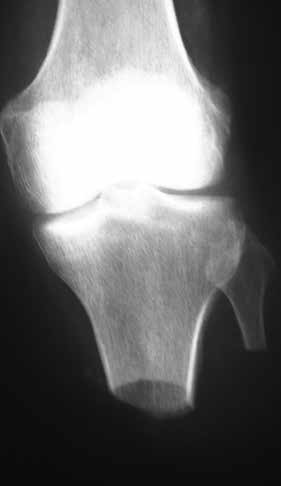

Sehr lange Unterschenkelstümpfe (kurz oberhalb der Spongiosa der distalen Tibia) sind auf die Dauer wegen der Gefahr zunehmender trophischer Störungen über die Jahre auch bei sehr geringem Endkontakt in der Prothese problematisch (Abb. 11). Viele Jahre scheint ein langer US-Stumpf gut versorgbar zu sein, wenn die Amputation im Kindesalter stattfindet und wenn Tibia- und Fibulaende sich fast auf gleicher Höhe befinden und somit eine breitere Auflagefläche für den Endkontakt darstellen (Abb. 12). Gewebe und arterielle Durchblutung stellen sich offenbar im Kindesalter auch besser auf die Gesamtsituation ein. Allgemein gilt aber: Der beste Unterschenkelstumpf ist der, der mit Muskulatur unter physiologischer Vorspannung gedeckt ist.